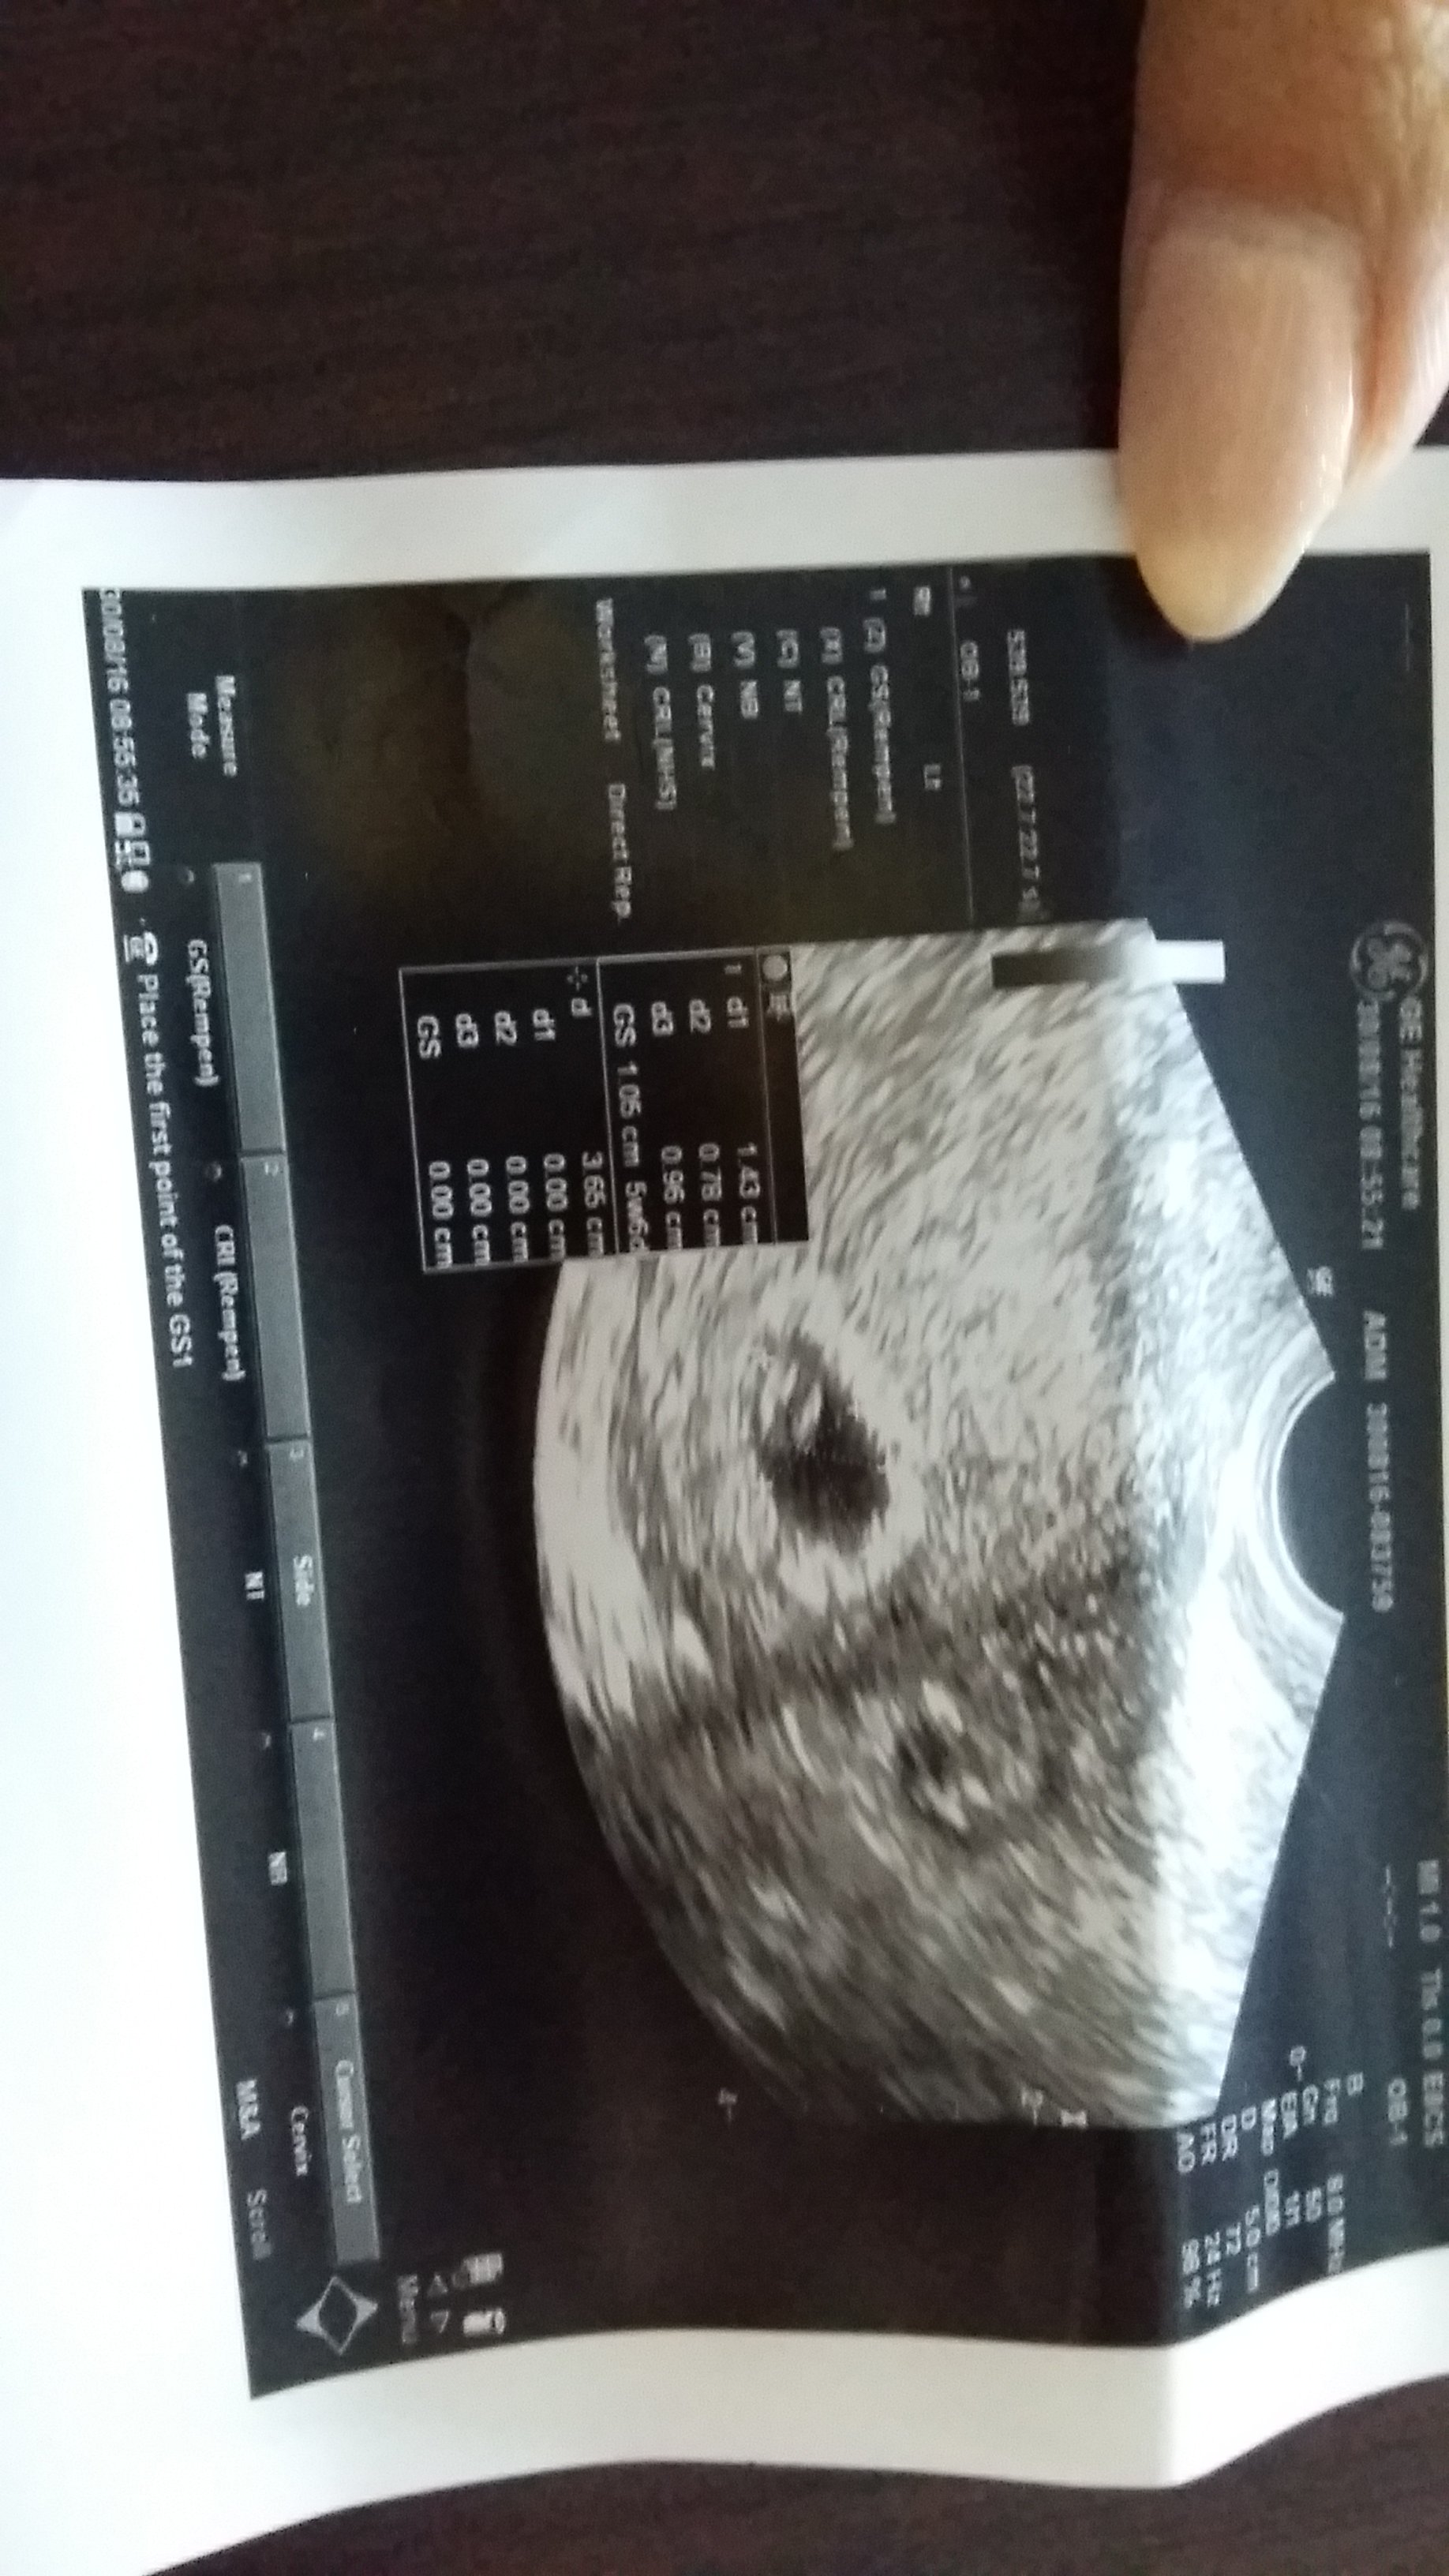

Ja już po wizycie;) serduszko biło chociaż krewetka bardzo malutka 2.5mm. Ciąża młodsza o tydzień czyli 5t6d. 14 września mam kolejną wizytę;)

Napisane na GT-I9506 w aplikacji Forum BabyBoom